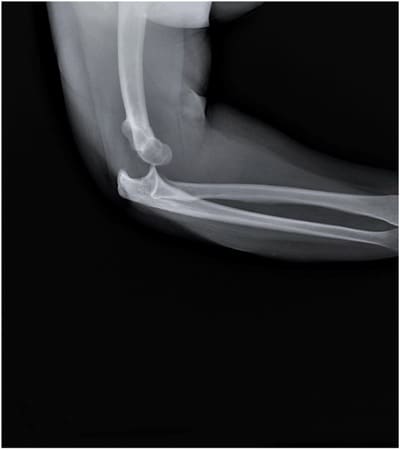

A dislocation is an injury caused by the separation of two bones where they meet the joint. Any joint in the body could be dislocated. When the bones of a joint are only partially separated, the resulting injury is called a subluxation. According to the University of Pennsylvania Health System, dislocation injuries are most commonly identified in the following joints:

- Elbows;

Physicians can sometimes identify a joint dislocation by performing a simple physical examination. However, some dislocations can only be detected with an X-ray or MRI. Insurance policies do not always cover these procedures; even when they do, patients may be required to pay expensive co-pays and deductibles. The Dietrich Law Firm P.C. believes that nobody should ever have to pay the price for another person’s negligence. We could help you investigate the causes of your Erie, Pennsylvania, dislocation accident, building the compelling, evidence-based claim for recompense you need to prevail in insurance negotiations or in court. Please send us a message online or call us today at 814-839-3939 to schedule your free, no-obligation consultation.